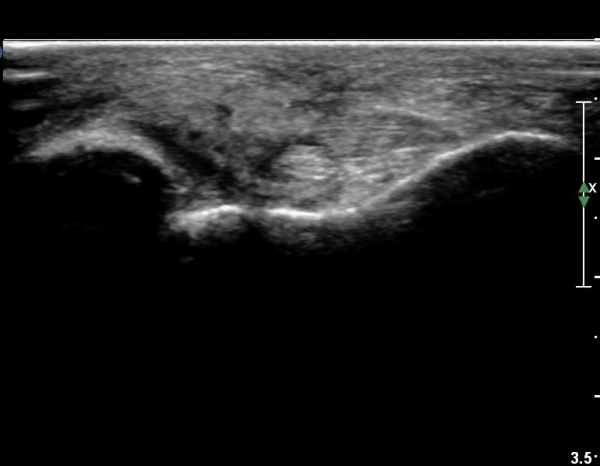

Àü°ÅºñÀδë Á¾´Ü¸é°Ë»ç¿¡¼­  Àü°ÅºñÀδëÀÇ ÆÄ¿­À» º¸ÀÓ(»çÁø 2).